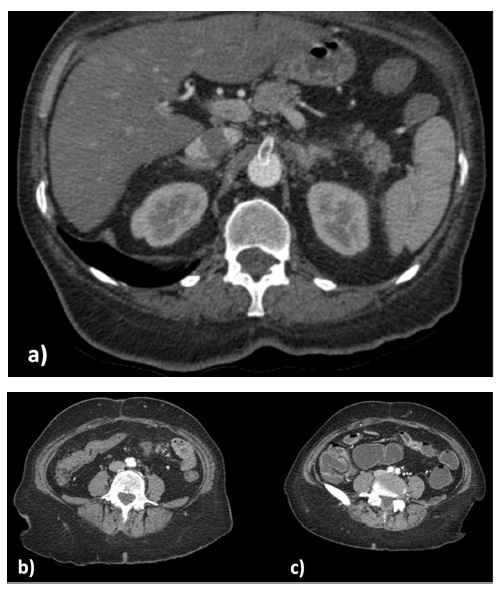

In the following three months, she tolerated food well. However, she needed to resort to the hospital again due to a one-month history of postprandial vomiting and abdominal pain worsening in the last 15 days. A CT angiography (CTA) was performed, showing a SMA stent thrombosis, compromised distal flow, and thickening of the small bowel with a stenosis in the preview entero-enteric anastomosis (figure1).

Figure 1 a) SMA stent thrombosis; b) inflammation and edema of intestinal wall; c) stenosis of 5 cm ileon extension.